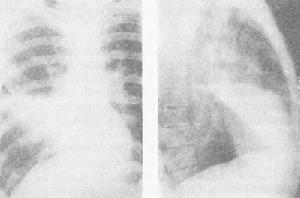

多重肺部感染多重肺部感染

多重肺部感染多重肺部感染治療